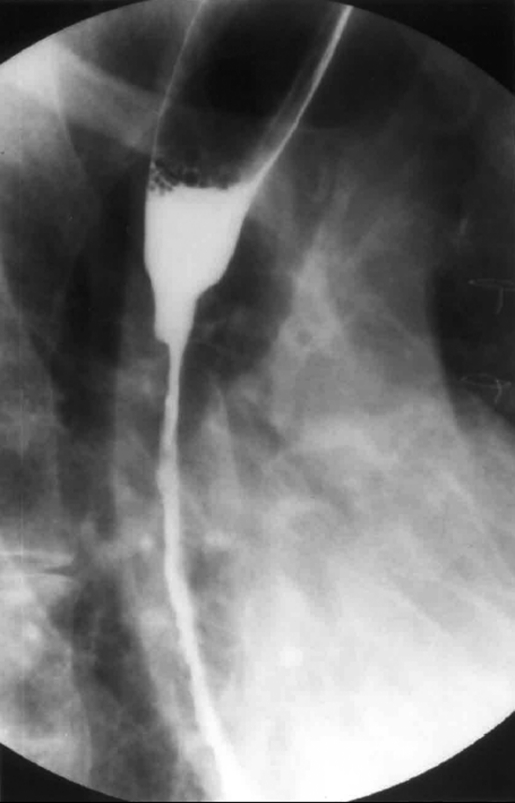

Postoperative stricture development at the esophagogastric anastomosis (Courtesy Dr. V. Penopoulos)